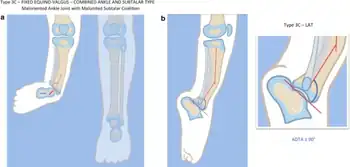

| a, b) Paley type 3c fibular hemimelia | |

Fibular hemimelia or longitudinal fibular deficiency is "the congenital absence of the fibula and it is the most common congenital absence of long bone of the extremities."[1][2] It is the shortening of the fibula at birth, or the complete lack thereof. Fibular hemimelia often causes severe knee instability due to deficiencies of the ligaments. Severe forms of fibula hemimelia can result in a malformed ankle with limited motion and stability. Fusion or absence of two or more toes are also common.[3] In humans, the disorder can be noted by ultrasound in utero to prepare for amputation after birth or complex bone lengthening surgery. The amputation usually takes place at six months with removal of portions of the legs to prepare them for prosthetic use. The other treatments, which include repeated corrective osteotomies and leg-lengthening surgery (Ilizarov apparatus), are costly and associated with residual deformity.[4]

- Absence of the lateral part of the ankle joint (due to absence of the distal end of the fibula), and what is left is unstable; the foot has an equinovalgus deformity